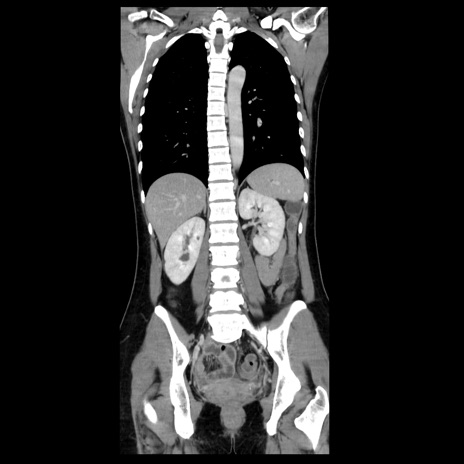

症例39(冠状断像)

【症例】40歳代女性

【主訴】上下腹部痛

【現病歴】2日目から下腹部痛あり。夜間は痛みで眠れなかった。昨日より上腹部痛と下痢が出現。臥位で痛みは軽快したため、休んでいた。本日になって臥位でも立位でも痛みが強くなってきたため救急要請。

【既往歴】子宮内膜症

【身体所見】部:平坦・軟、左上下腹部に圧痛あり、反跳痛あり。

【データ】WBC 21800、CRP 26.78

CT